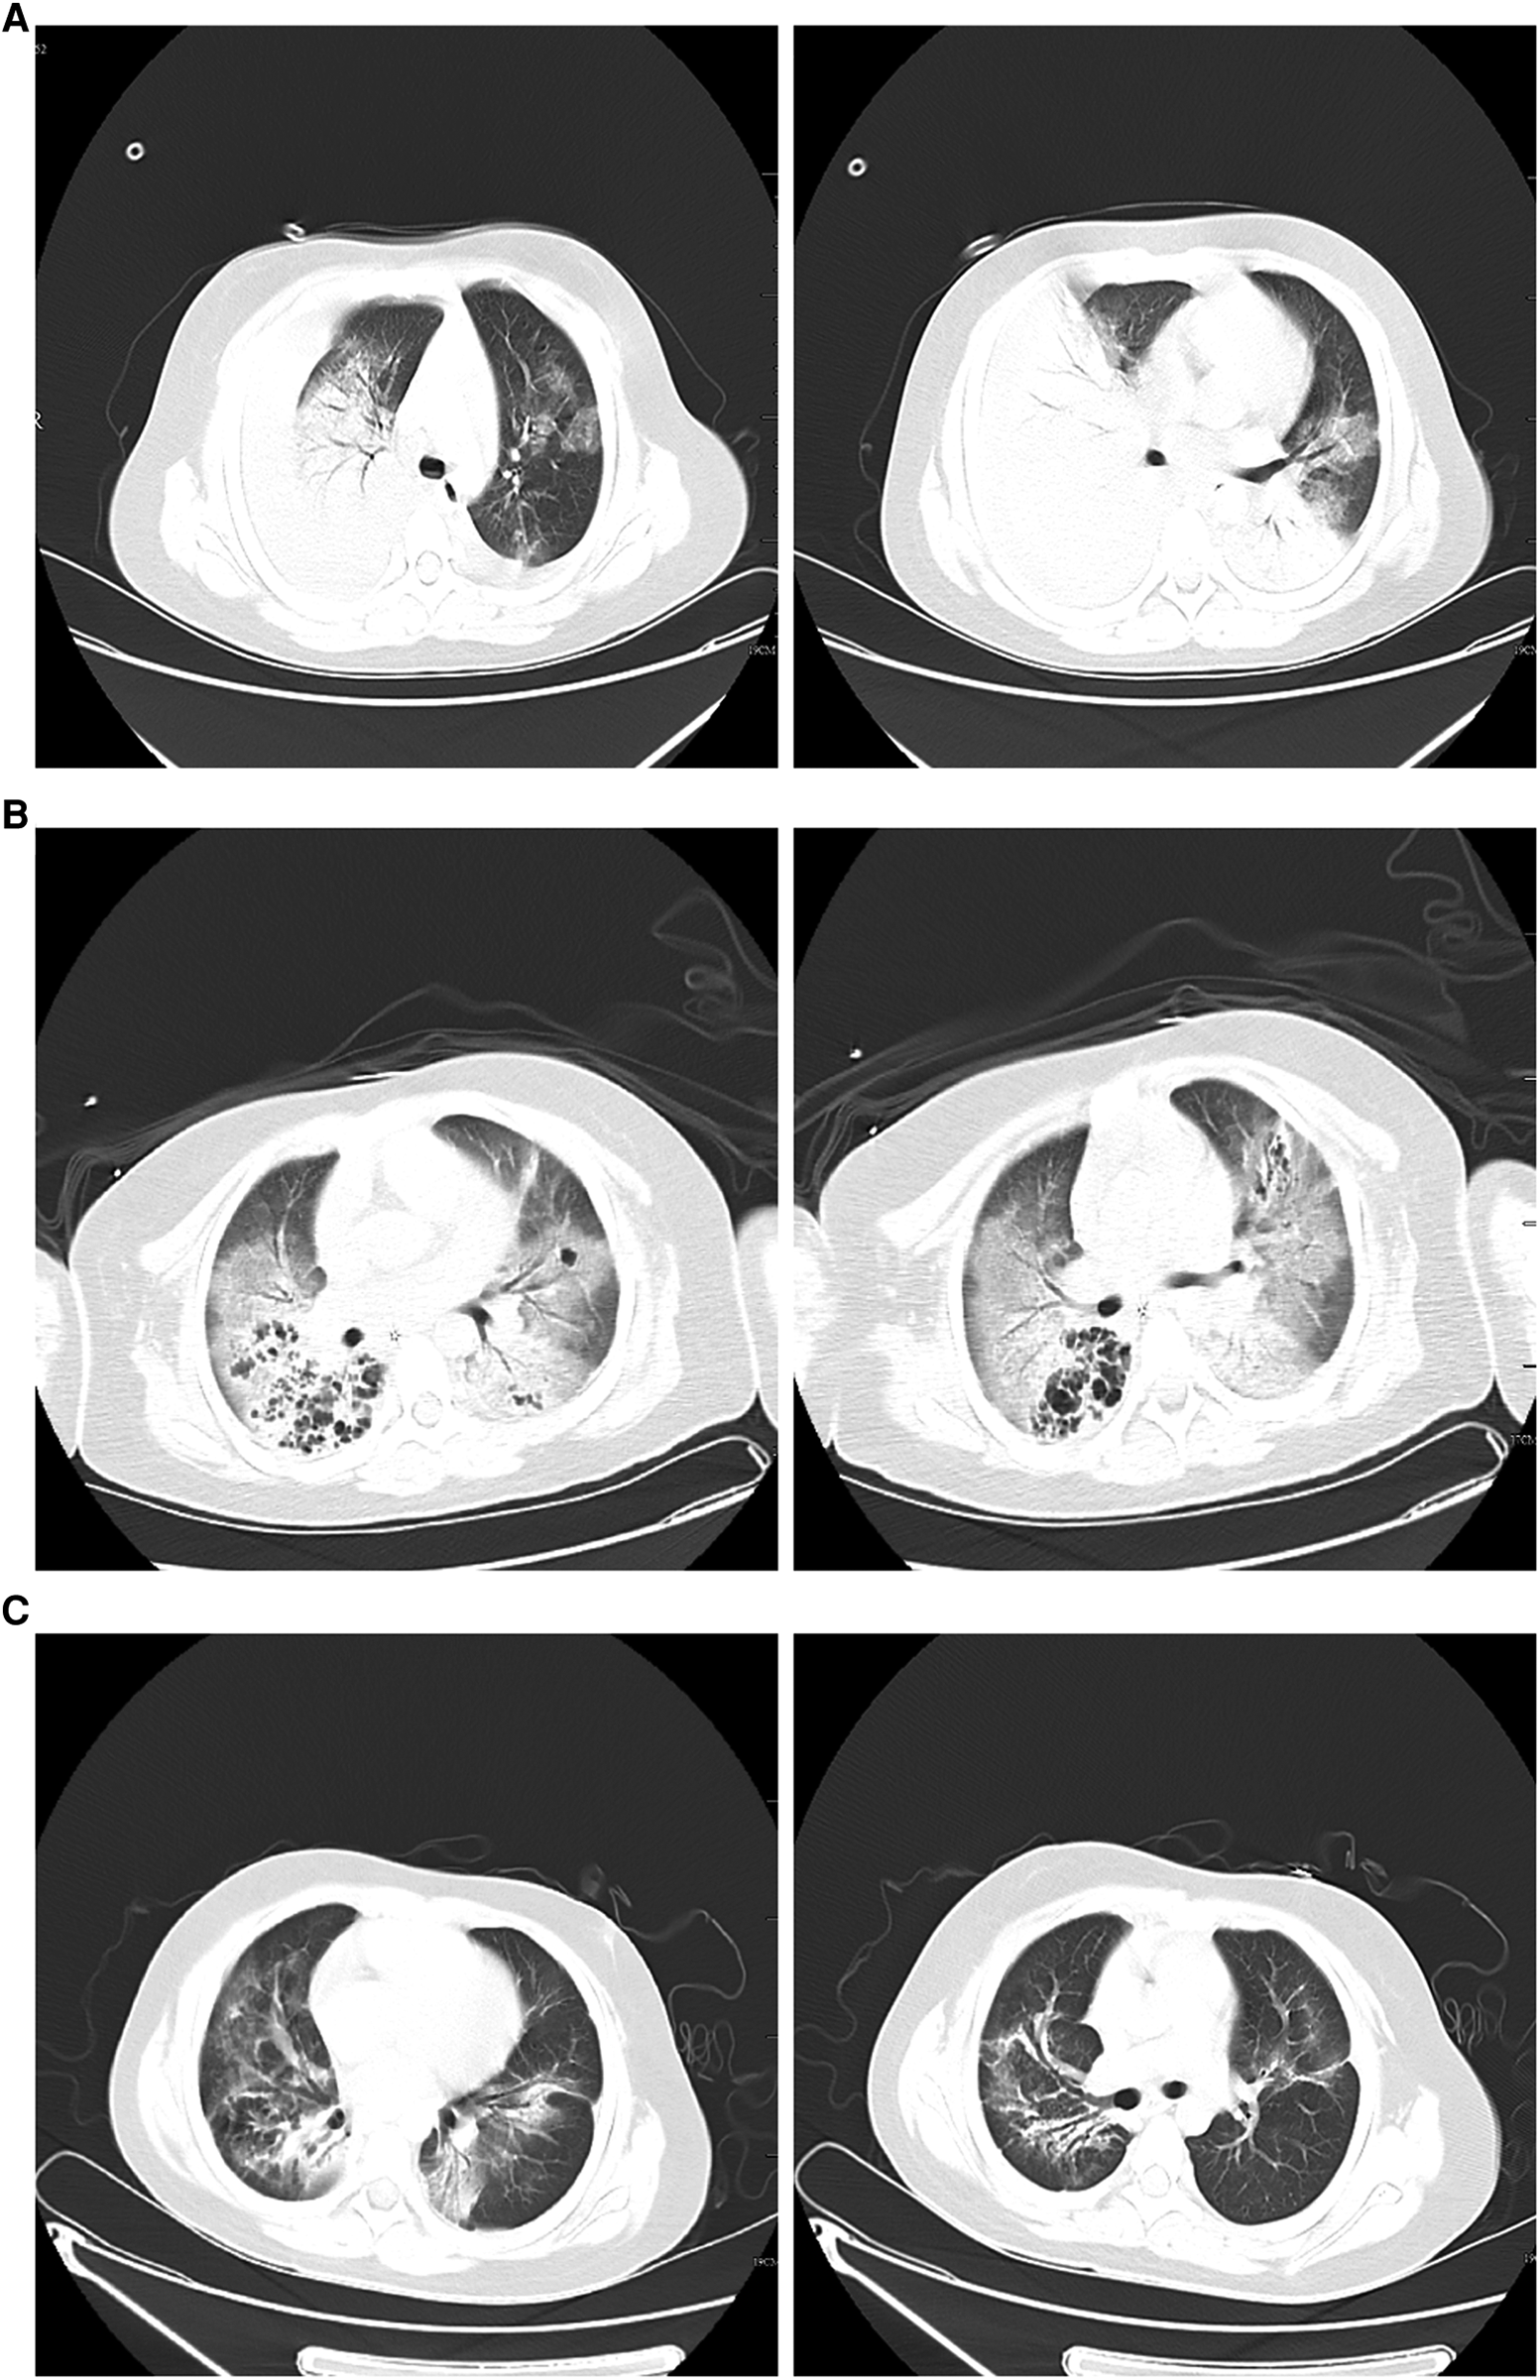

An 8-year-old girl presented to a hospital pediatric emergency department with a 1-week history of cough, fever for 4 days, and dyspnea for 5 h, without any response to oral cephalosporins. When she was admitted to the hospital, she had shortness of breath, 50 beats per minute, fever, 38.3 °C, tachycardia, 154 beats per minute, and hypoxemia, 72% in ambient air. Physical examination revealed moist rales in the left lung and diminished breath sounds over the right lung. Leukocyte count was 19 × 109/L, indicating leukocytosis of mainly neutrophils, and C-reactive protein level was 0.2 mg/dl. Blood biochemical analysis showed that the level of alanine aminotransferase was 516 U/L, lactate dehydrogenase was 2113 U/L, and sodium ions was 122 mmol/L. Chest x-ray photograph showed diffuse opacification on the left lung, Atelectasis was observed in the right lung with a large effusion in the right pleural cavity (Figure 1). She received a combination of antibiotics (azithromycin and ceftriaxone) to treat severe pneumonia and was transferred to the pediatric intensive care unit (PICU) for further treatment. There, she was given high-flow warm humidified oxygen through the nose. A computed tomography (CT) scan of the chest showed bilateral lung infection and right lung consolidation density; Multiplelymph nodes in the mediastinum show that the area is slightly larger; Bilateral pleural effusion (Figure 2A). Ultrasonic examination also showed a large amount of pleural effusion in the right lung. Lower chest puncture drainage was performed under ultrasound guidance, and antibiotic therapy was escalated to cefoperazone sodium, sulbactam sodium, and azithromycin. Analysis of pleural effusion showed that a protein level of 38.2 g/L, glucose of 6.57 mmol/L, lactate dehydrogenase of 3082 U/L, and mononuclear phagocyte predominance was observed. Negative bacterial culture results for blood, endotracheal aspirate and pleural effusion. Antigen testing for respiratory pathogens (including adenovirus, respiratory syncytial virus, influenza virus and EB virus) is suggestive of negative results. Polymerase chain reaction (PCR) showed that MP was positive in endotracheal aspirate and pleural effusion. MP-specific IgM and IgG antibodies from blood showed negative results. Acquired mutations on the ribosomal macrolide target were negative, suggesting that it was not a macrolide-resistant strain. Further medical history obtained from family members did not indicate any risk factors for tuberculosis; however, a gamma release assay was also sent for analysis. On the first day of admission, patient was found to have abnormal coagulation function, and bleeding spots appear on the skin the next day. In the coagulation profile, the international normalized ratio was 1.67, with a partial thromboplastin time of 31.5 s and a prothrombin time of 17.5 s. Thrombin time was 60.0 s. The fibrinogen function K value was 18.1 min, the fibrinogen and platelet function (angle) were 27.9, the platelet function was 21.2 mm, and the comprehensive index of coagulation function was −14.5. In order to exclude hematologic diseases, coagulation factors and plasma correction tests were added, and fresh frozen plasma and fibrinogen infusions were given, and the coagulation function was slightly improved. After 48 h, she remained febrile with worsening tachypnea and hypoxic respiratory failure, hemoptysis, and required intubation and ventilation. Blood was visible in the airway, and bronchoscopy and bronchoalveolar lavage revealed DAH. Therefore, a diagnosis of severe MP in conjunction with DAH, severe pediatric acute respiratory distress syndrome (ARDS), and acute hypoxic respiratory failure was established. Human blood immunoglobulin, epinephrine endotracheal instillation, and intravenous application of glucocorticoids were administered.

Figure 2

(A) Chest computed tomography scan on hospitalization day 1 showing double lung infection and right lung consolidation density; multiple lymph nodes in mediastinum the mediastinum show that the area is slightly larger; bilateral pleural effusion. (B) After 8 days of therapy, a computed tomography scan of the chest shows exudate changes in both lungs, partial consolidation in the right lung, similar lesions as initially observed, interstitial changes in the right lower lung with multiple bronchial cystic changes, and reactive lymphadenopathy. (C) Forty-five days after hospital discharge, the pulmonary lesions on computed tomography were significantly absorbed compared to earlier.

On the 9th day, the patient had low-grade fever; sputum culture, blood mNGS testing, and G test suggested Candida albicans infection, and fluconazole antifungal therapy was administered for 10 d. Other infectious organism was not found in repeated respiratory tract, blood cultures andpleural cultures. After 8 d of therapy, CT of the chest revealed exudative changes in both lungs, partial consolidation in the right lung, similar to the range of lesions as before, interstitial changes in the right lower lung with multiple bronchial cystic changes, and reactive lymphadenopathy (Figure 2B). After 12 d of therapy, the patient clinically improved and became afebrile. Ventilator use was discontinued, and she was discharged from the hospital 15 d after extubation without supplemental oxygen. Pulmonary CT review 45 days after discharge indicated that the lesion was significantly absorbed compared to the lesion in the previous CT scan (Figure 2C).